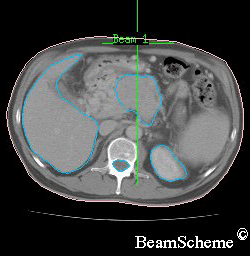

This picture is of the bottom of the rib cage.

on the left is a large crescent – this is the liver

on the right, at the bottom, is a round shape – this is the kidney

in the centre, at the bottom, is a smaller round shape – this is the spinal cord inside the backbone

in the middle is an irregular shape – this is the pancreas with a cancer inside it

One beam is aimed from in front of the patient. This is the beam at the top of the picture.

The other two beams are aimed from the sides at an angle so that they avoid the spinal cord and kidney.